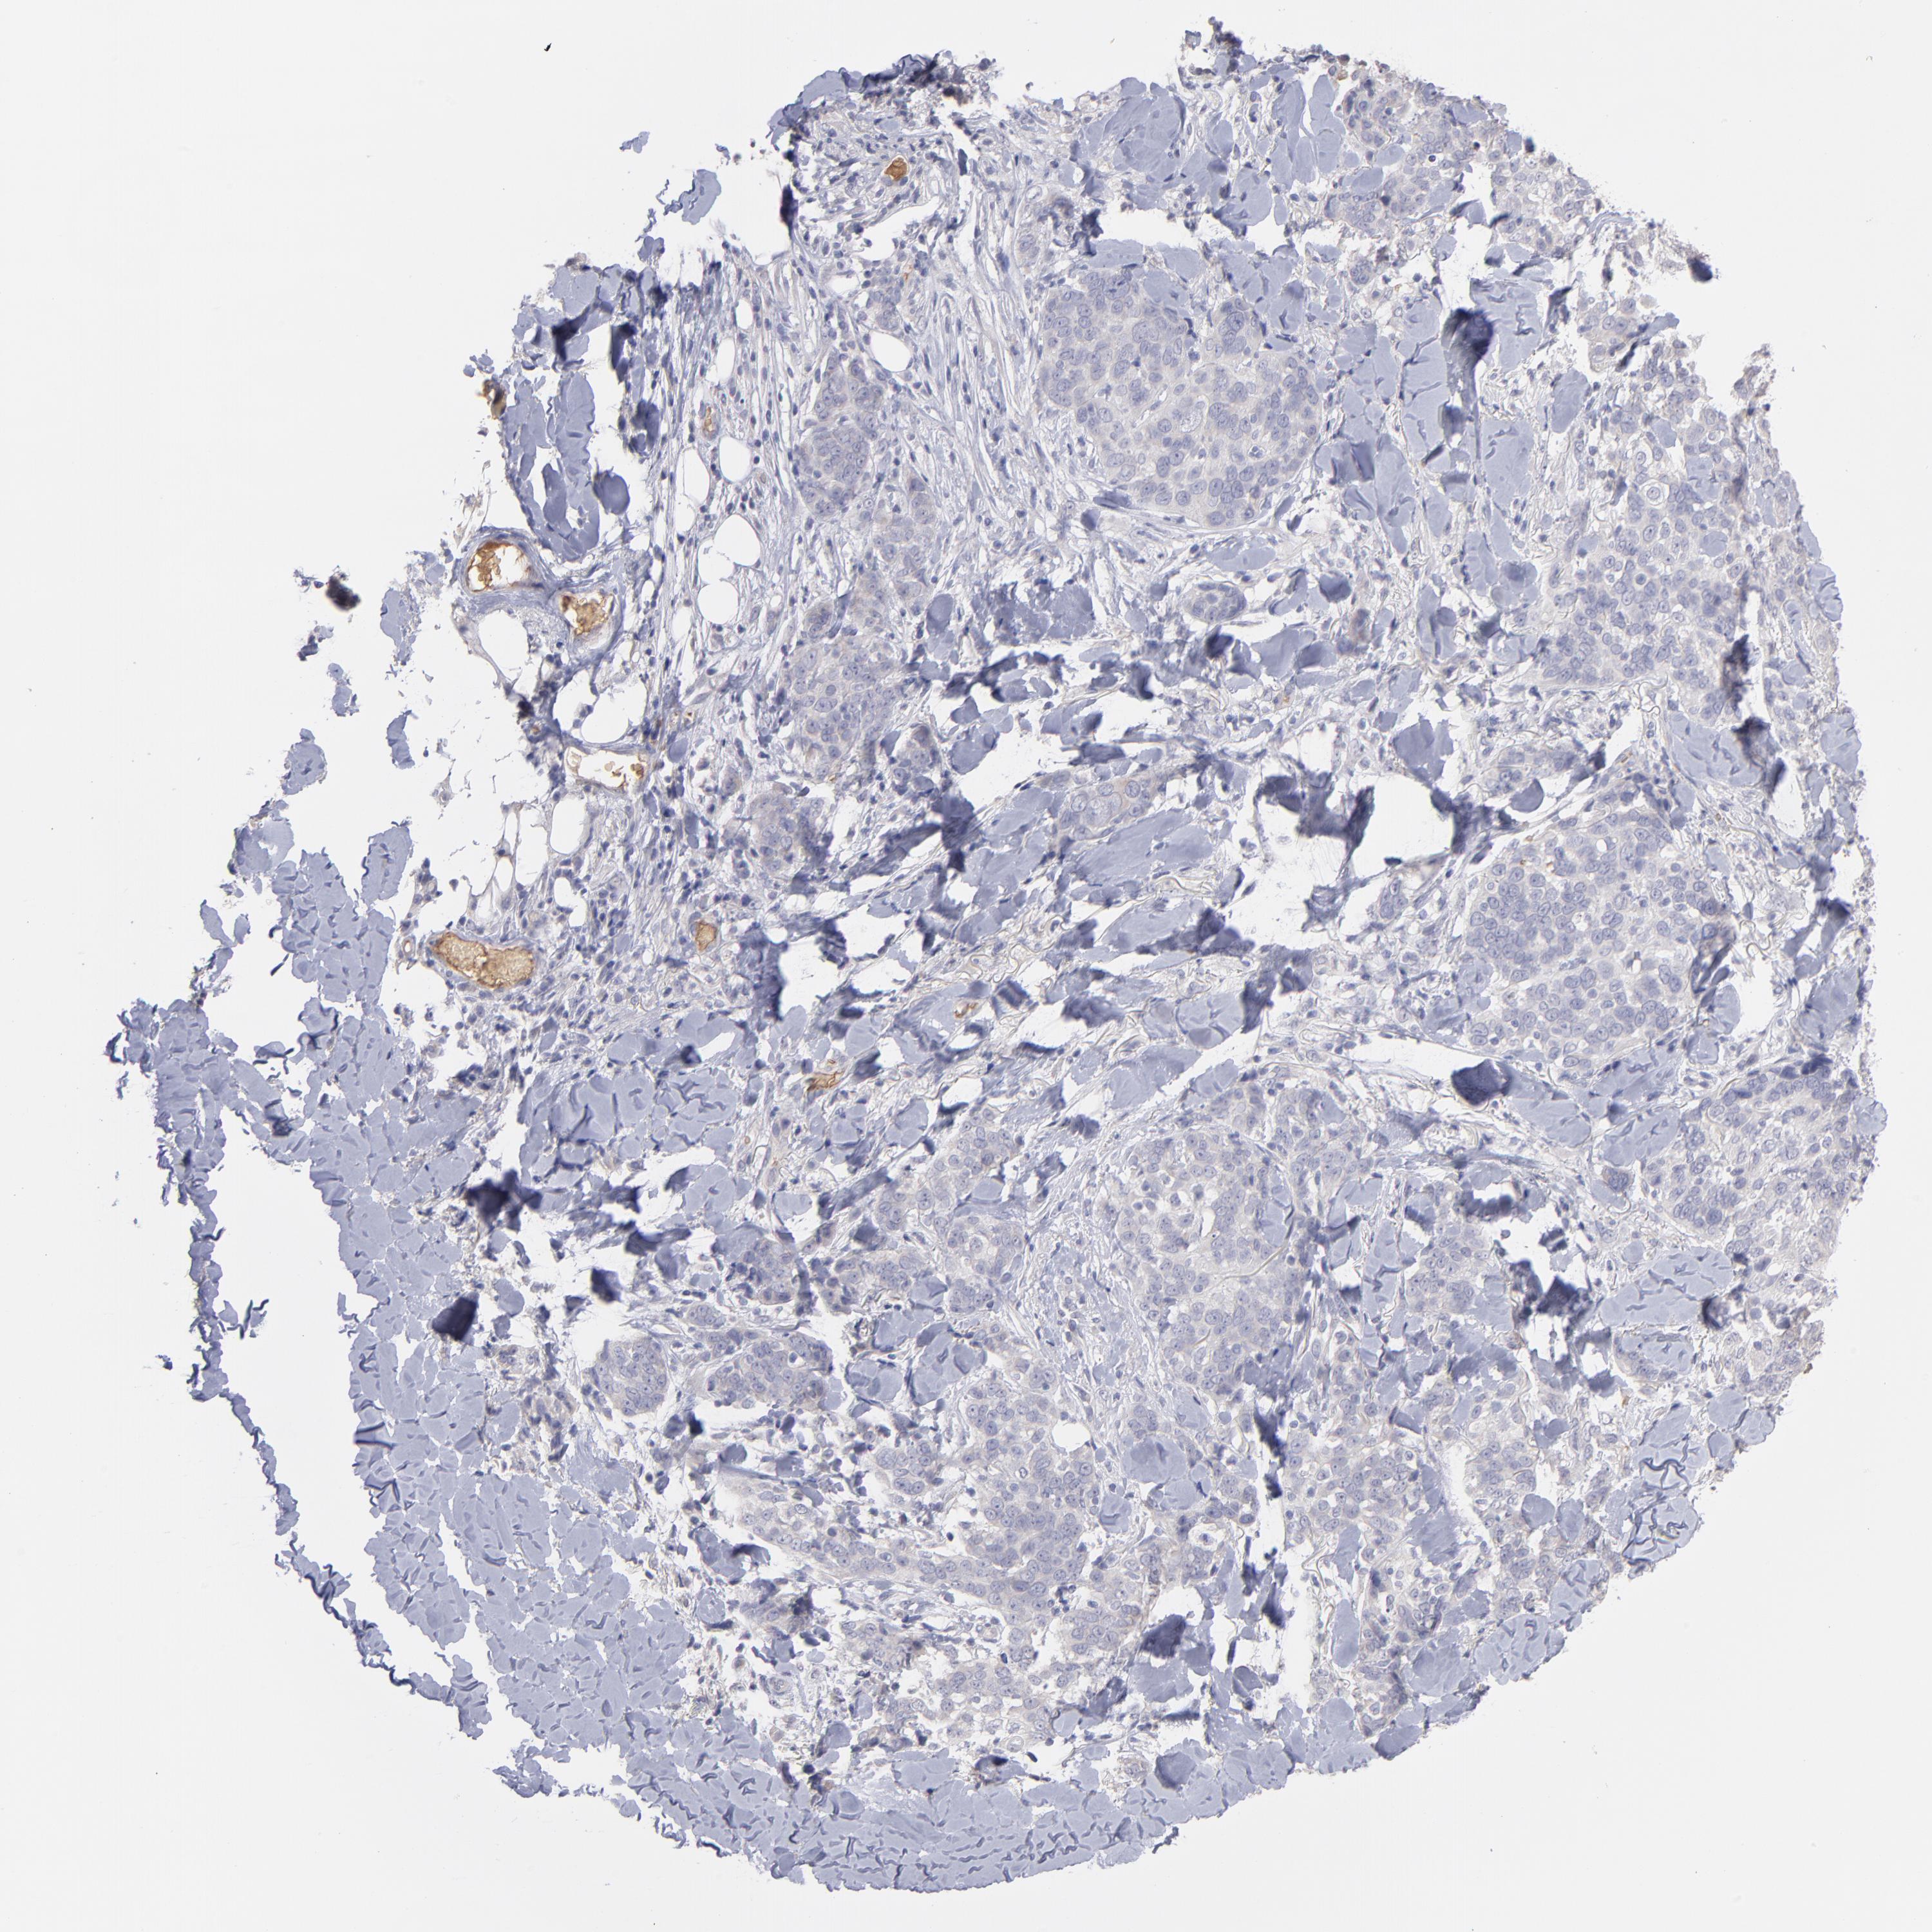

Basal cell and squamous cell cancer

SKIN CANCER - Protein expressioni

A mouse-over function shows sample information and annotation data. Click on an image to view it in a full screen mode. Samples can be filtered based on level of antibody staining by selecting one or several of the following categories: high, medium, low and not detected. The assay and annotation is described here.

Antibody stainingi

Antibody staining in the annotated cell types in the current human tissue is reported as not detected, low, medium, or high, based on conventional immunohistochemistry profiling in selected tissues. This score is based on the combination of the staining intensity and fraction of stained cells.

Each image is clickable and will lead to virtual microscopy that enables deeper exploration of all samples and also displays staining intensity scores, fraction scores and subcellular localization as well as patient and tissue information for each sample.

Antibody HPA003827

Antibody HPA052139

Squamous cell carcinoma, NOS

Basal cell carcinoma